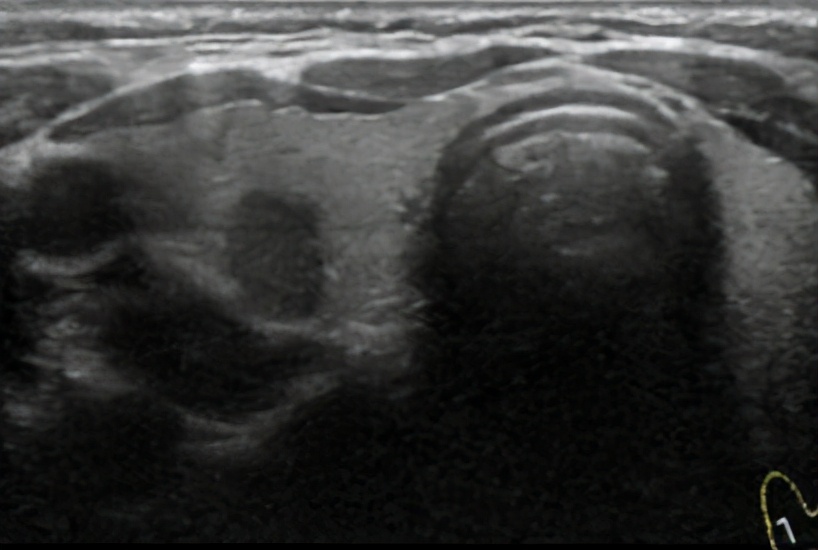

无回声: 遇到的组织有液体,一般反应是没有回声,比如临床上观察到的囊性结节等,一般为良性组织,囊性组织越多,良性概率越高;

低回声: 遇到的组织是实体组织,但没有硬性积集,反应会是低的回声,低回声可见于各种良恶性的结节,但并不是明显的恶性特征;

极低回声: 是一种低于颈前肌肉群的回声,在超声上的显影是颜色最暗的,极低回声通常可以作为明显的恶性特征;